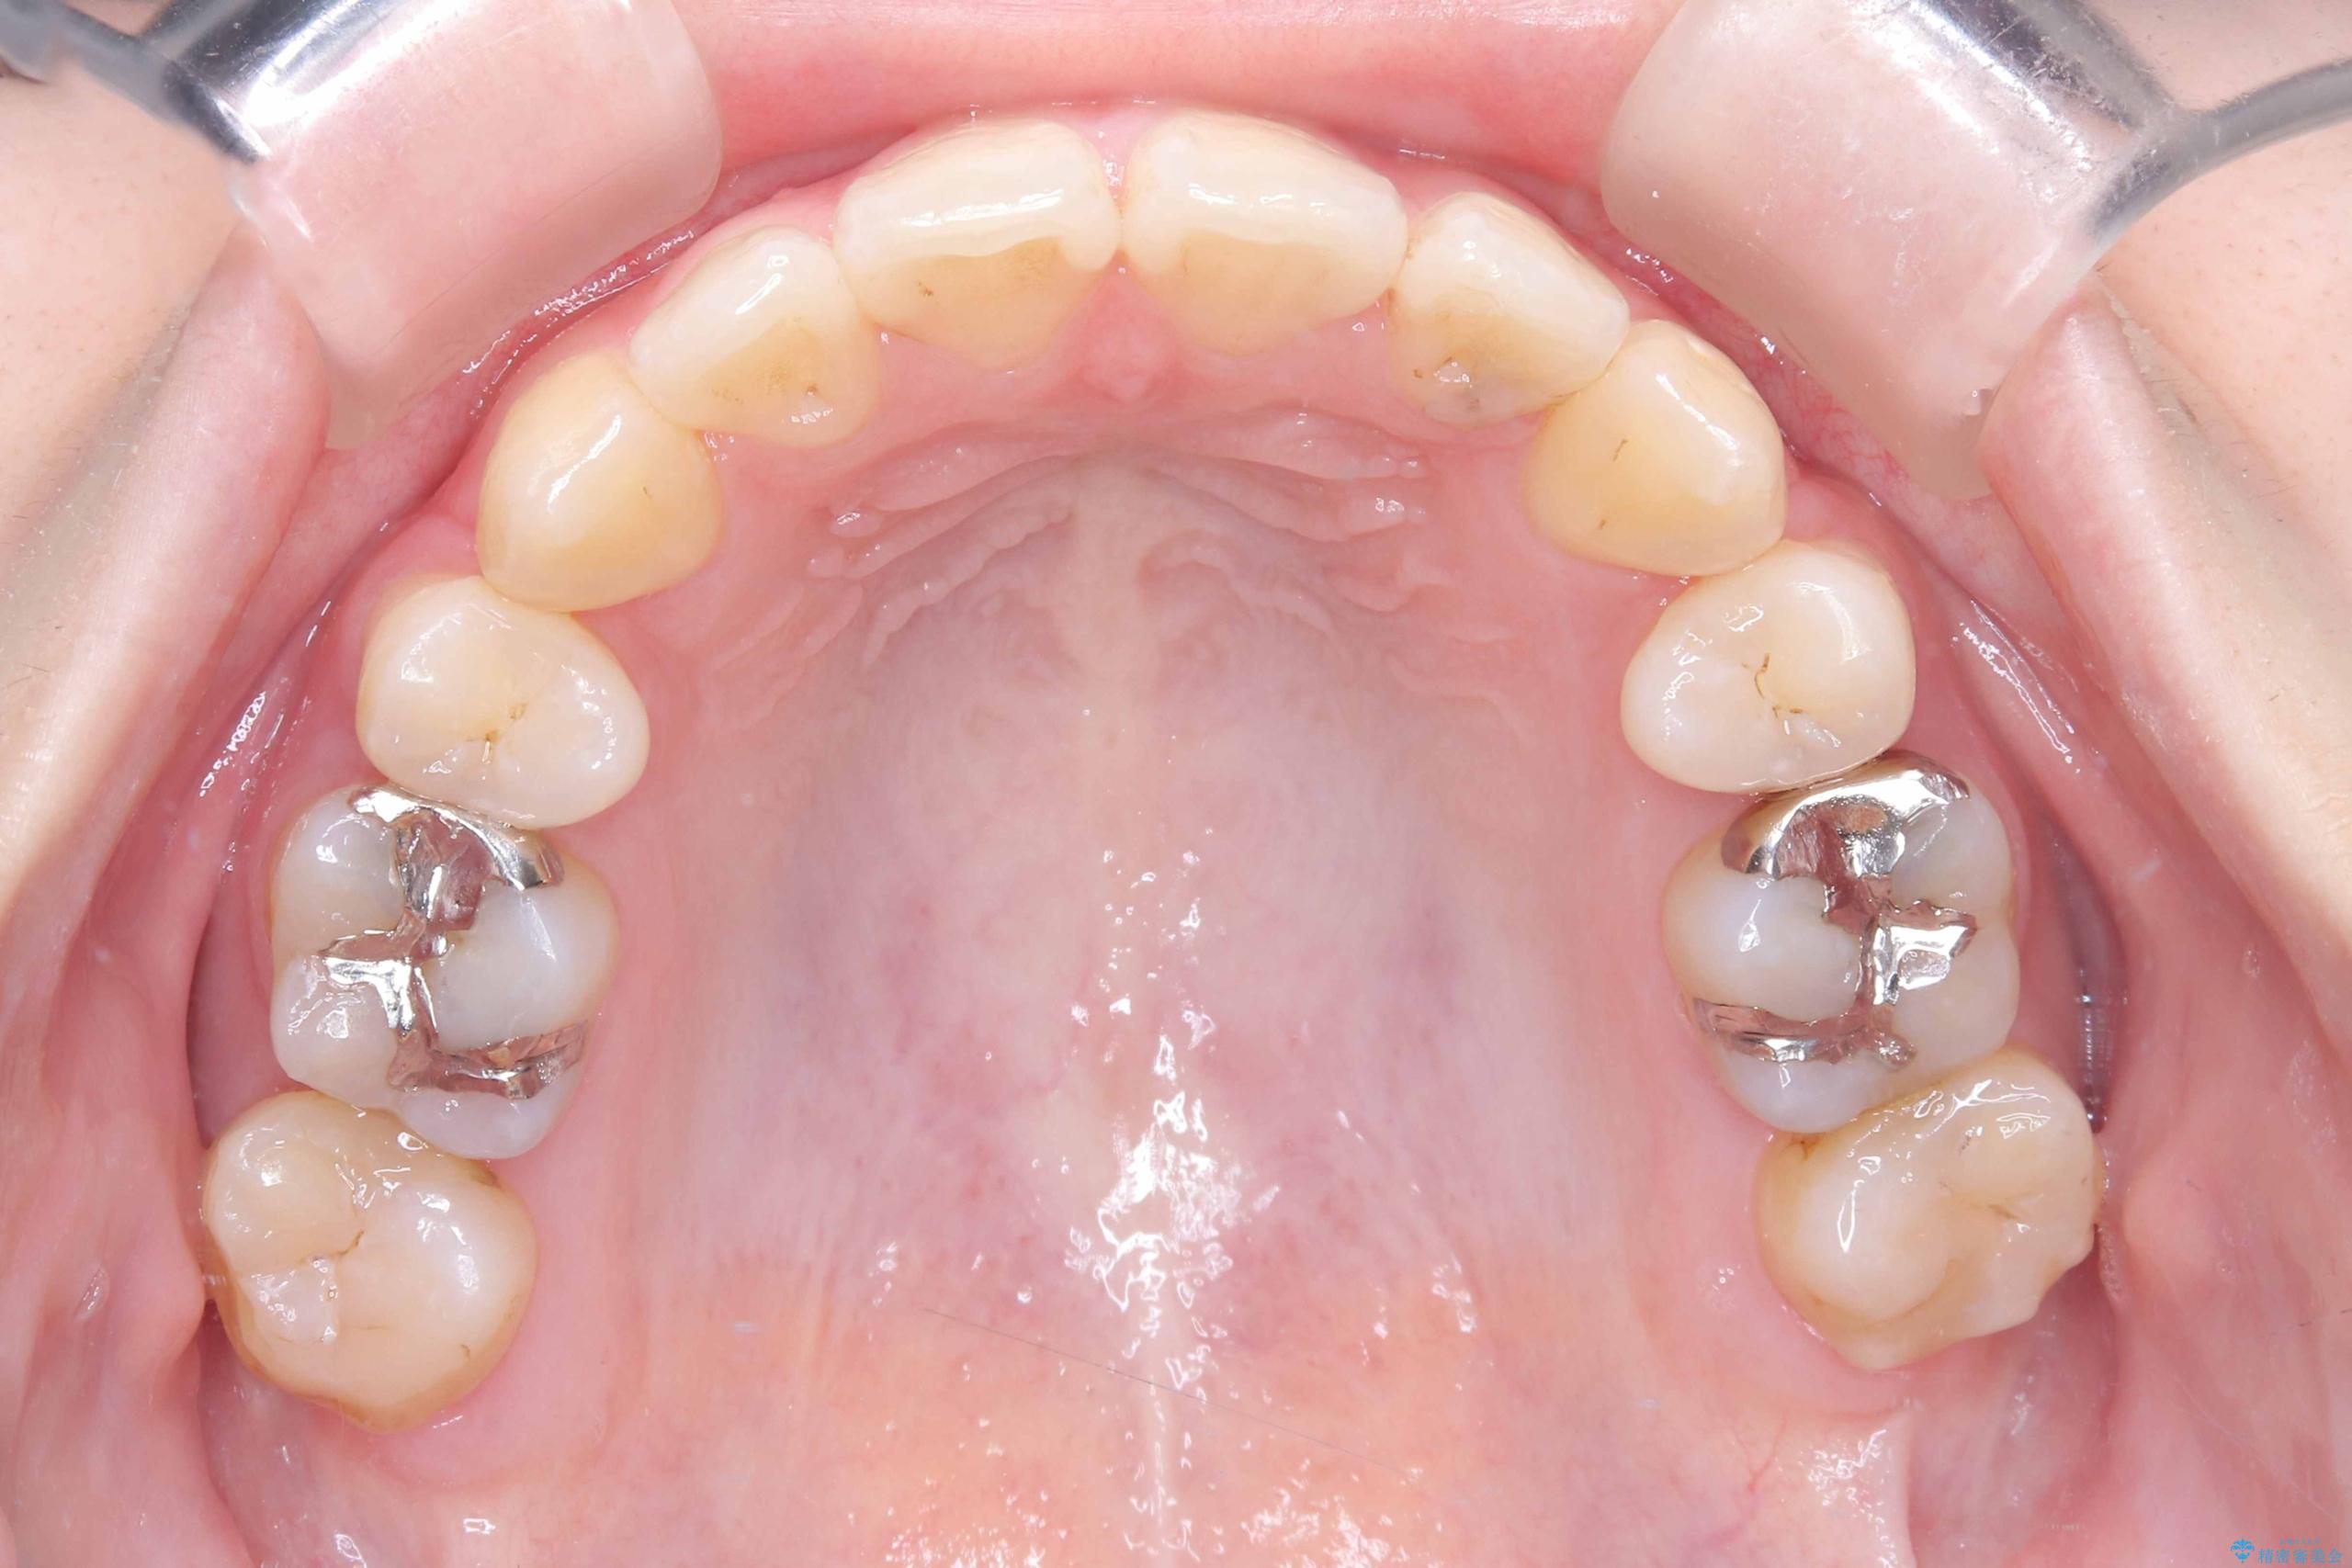

- 開咬と歯のデコボコ(叢生)、八重歯を主訴にご来院された患者様です。

矯正の精密検査の結果、上顎左右4番および下顎左右5番の計4本を抜歯し、ワイヤー矯正(クリア装置)にて治療を行いました。

虫歯があったので、虫歯治療は矯正前に行っています。